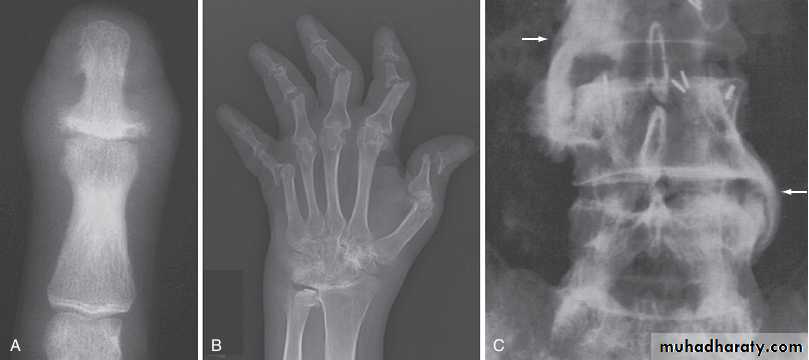

In established AS, radiographs of the sacroiliac joint show irregularity and loss of cortical margins, widening of the joint space and subsequently sclerosis, joint space narrowing and fusion.Lateral thoracolumbar spine Xrays may show anterior ‘squaring’ of vertebrae due to erosion and sclerosis of the anterior corners and periostitis of the waist.

Bridging syndesmophytes may also be seen. These are areas of calcification that follow the outermost fibres of the annulus

Investigations

In advanced disease, ossification of the anterior longitudinal ligament and facet joint fusion may also be visible. The combination of these features may result in the typical ‘bamboo’ spine.Erosive changes may be seen in the symphysis pubis, the ischial tuberosities and peripheral joints.

In chronic or recurrent disease, Xrays show periarticular osteoporosis, joint space narrowing and proliferative erosions.

Another characteristic feature is periostitis, especially of metatarsals, phalanges and pelvis, and large, ‘fluffy’ calcaneal spurs.

In contrast to AS, radiographic sacroiliitis is often asymmetrical and sometimes unilateral, and syndesmophytes are predominantly coarse and asymmetrical, often extending beyond the contours of the annulus (‘nonmarginal’)

Xrays may be normal or show erosive change with joint space narrowing. Features that favour PsA over RA include the characteristic distribution of proliferative erosions with marked new bone formation, absence of periarticular osteoporosis and osteosclerosis.

Imaging of the axial skeleton often reveals features similar to those in chronic reactive arthritis, with coarse, asymmetrical, nonmarginal syndesmophytes and asymmetrical sacroiliitis.